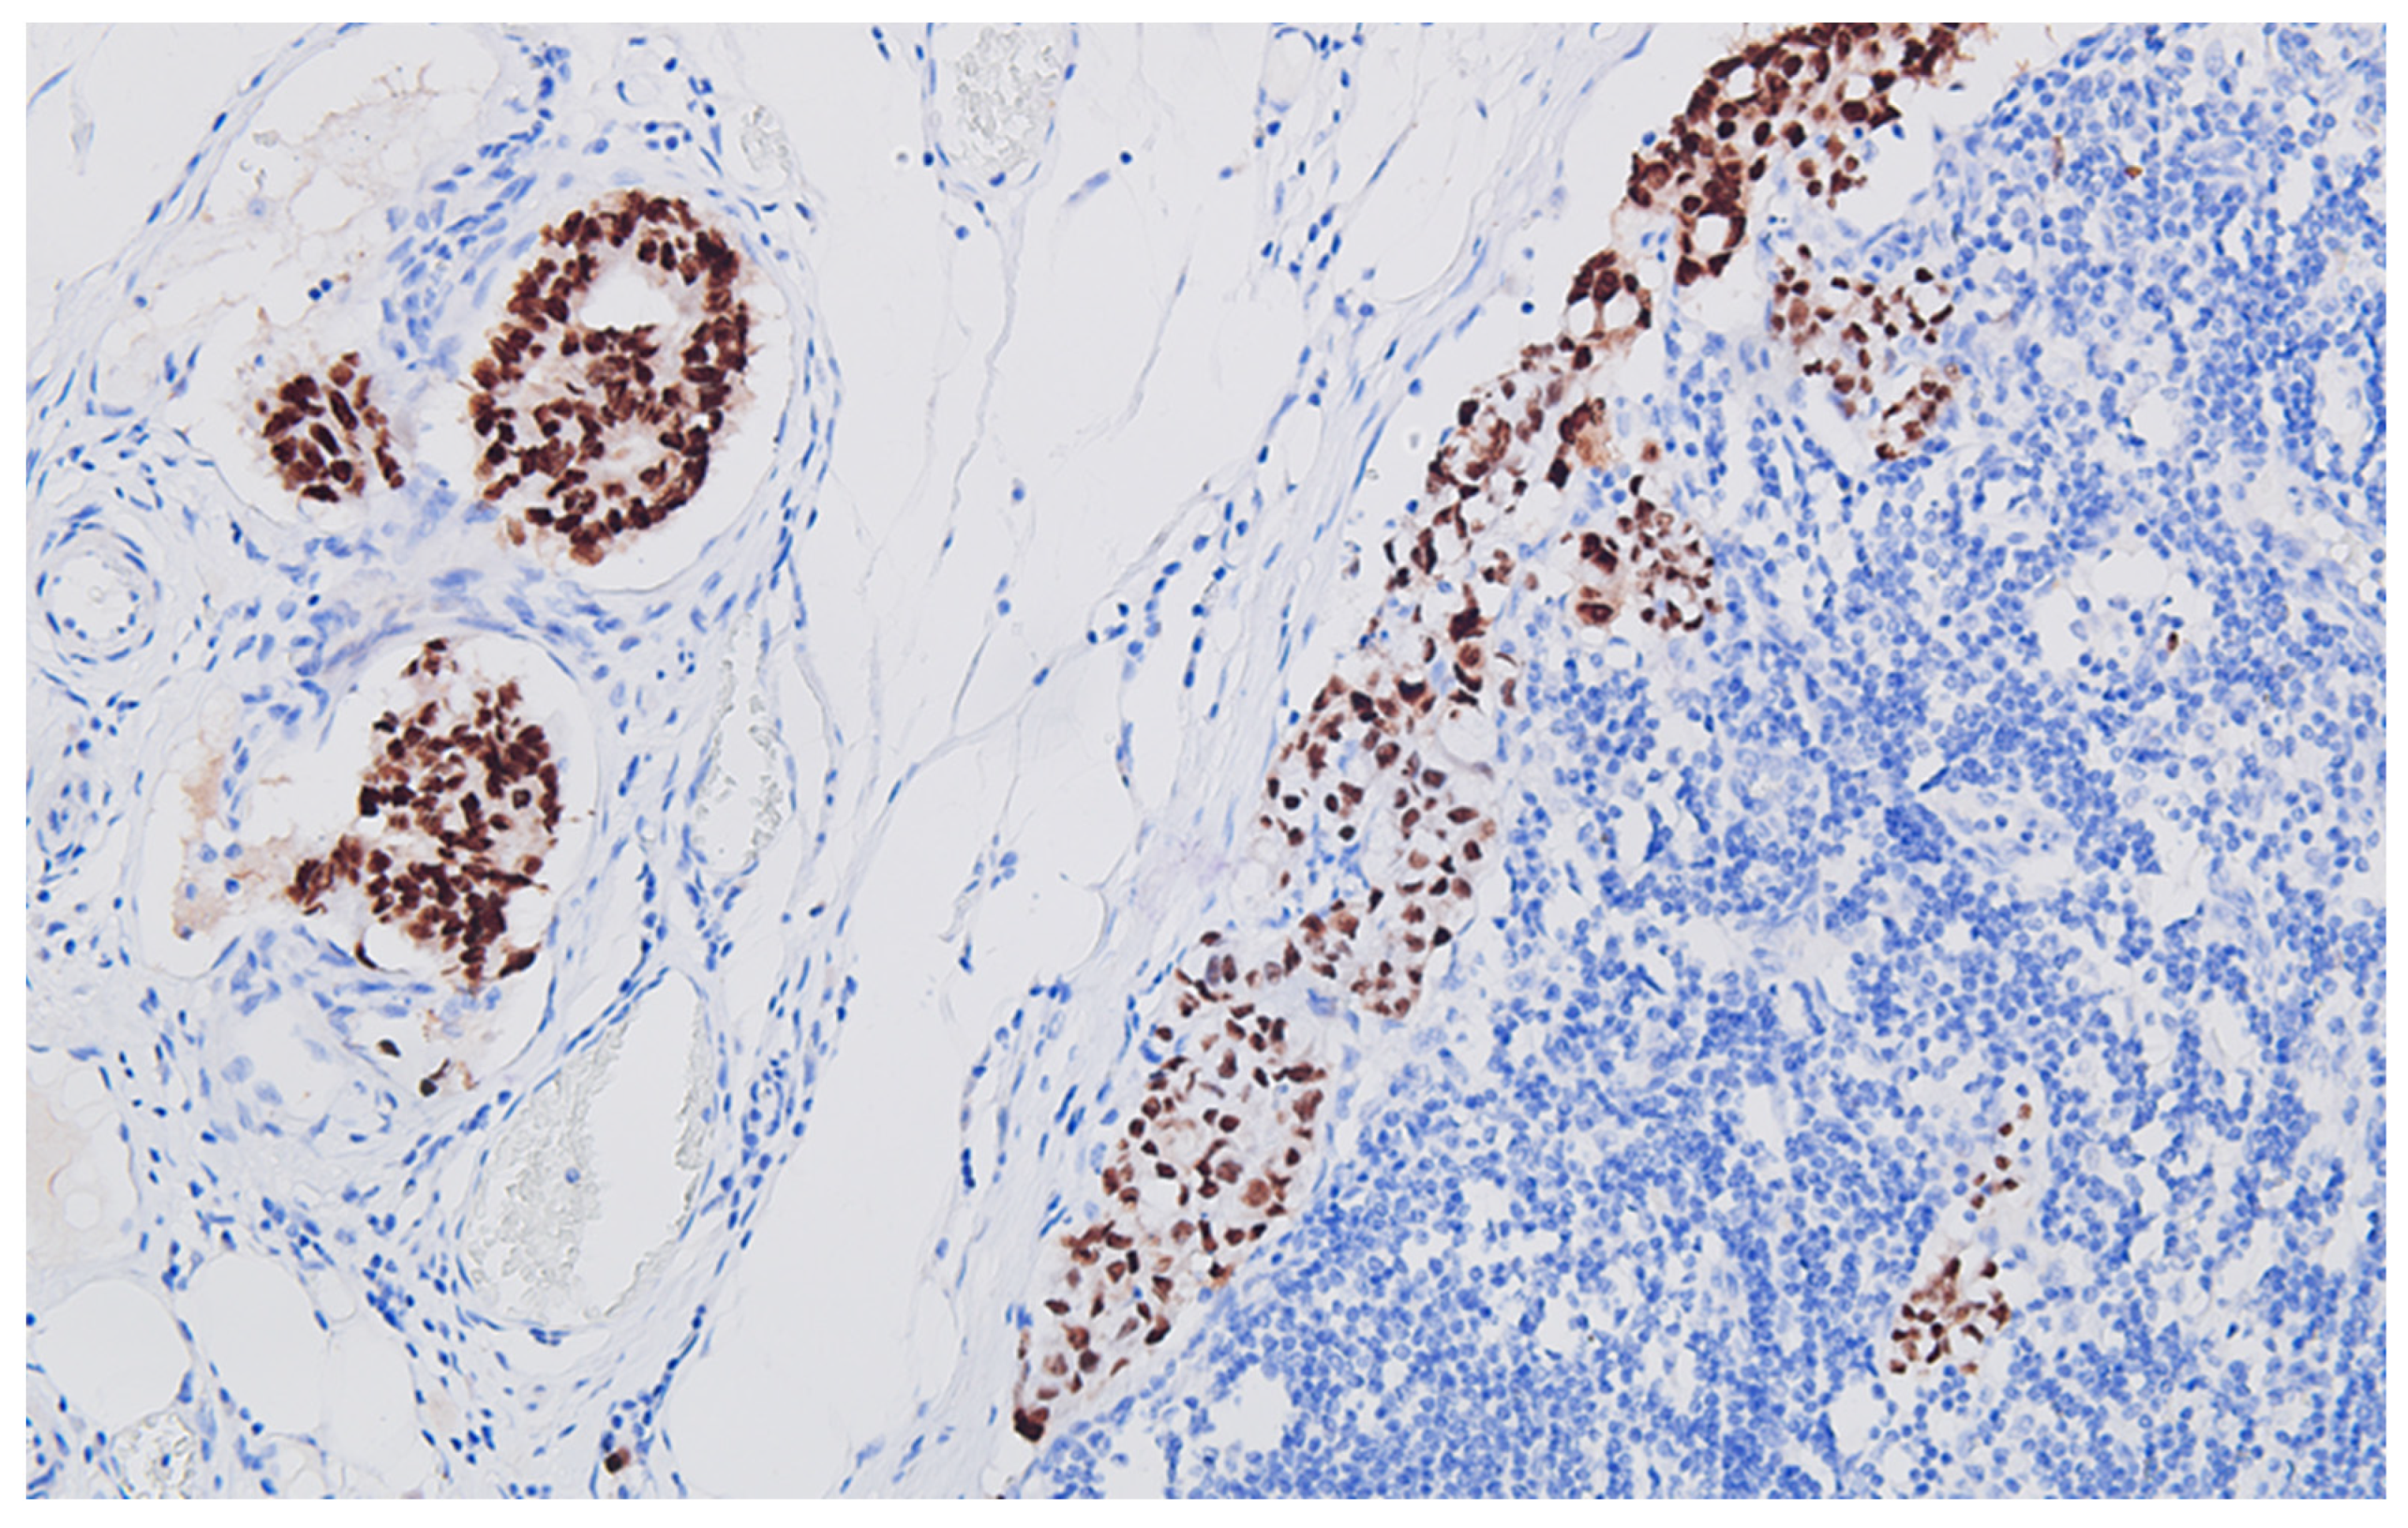

The immunohistochemical profile of the carcinoma CK7 negative, patchy CK20 positive (Figure 5), and diffuse CDX2 positive (Figure 6) corresponds to a primary colorectal carcinoma, and for the peritoneal tumor nodules, the diffuse S100 protein positivity (Figure 7) and patchy CD68 positive (Figure 8), together with CD117 (c-kit) negative reaction, leads to the diagnosis of granular cell tumor/granular cell nerve sheath tumor/Abrikossoff tumor and excludes a possible association of a gastrointestinal stromal tumor with the colonic carcinoma.

Figure 7.

Peritoneal granular cells tumor, with intense and diffuse positive reaction for S100 protein of the neoplastic cells, DAB ×200.

The histopathological report ruled out the clinical supposition of peritoneal carcinomatosis by unequivocally demonstrating (usual H&E stain and immune profile: S100+, CD68+) that the peritoneal nodules are composed of granular cells, without cyto-nuclear atypia, originating in the peripheral nerve sheath: granular cell nerve sheath tumor (Abrikossoff tumor). In addition, immunohistochemical profiling excluded the gastro-intestinal tumor, a very similar aspect on routine (H&E) staining with the granular cell tumor, by negative reaction to CD117 (c-kit) and positive S100, combined with patchy CD68 positive.